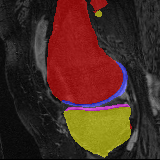

Moving Target Mono-0 Mono-5 DA-1 DA-5 Mono-200 Refer to caption Refer to caption Refer to caption Refer to caption Refer to caption Refer to caption Refer to caption Refer to caption Refer to caption Refer to caption Refer to caption Refer to caption Refer to caption Refer to caption

Figure 2:  Examples of knee MRI registration (top) and brain MRI segmentation (bottom) results. Top: The first two columns are the moving image/segmentation and the target image/segmentation followed by the warped moving images (with deformation grids)/segmentations by different models. Bottom left to right: original image, manual segmentation, and predictions of various models. Mono-i𝑖i and DA-i𝑖i represent the mono- and DA models with i𝑖i manual segmentations respectively.

Moving Target Mono-0 Mono-21 DA-1 DA-21 Mono-65 Refer to caption Refer to caption Refer to caption Refer to caption Refer to caption Refer to caption Refer to caption Refer to caption Refer to caption Refer to caption Refer to caption Refer to caption Refer to caption Refer to caption

Figure 4: Examples of brain MRI registration (top) and knee MRI segmentation (bottom) results. Top: The first two columns are the moving image/segmentation and the target image/segmentation followed by the warped moving images/segmentations by different models. Bottom left to right: original image, manual segmentation, and predictions of various models. Mono-i𝑖i and DA-i𝑖i represent the mono- and DA models trained with i𝑖i manual segmentations respectively.